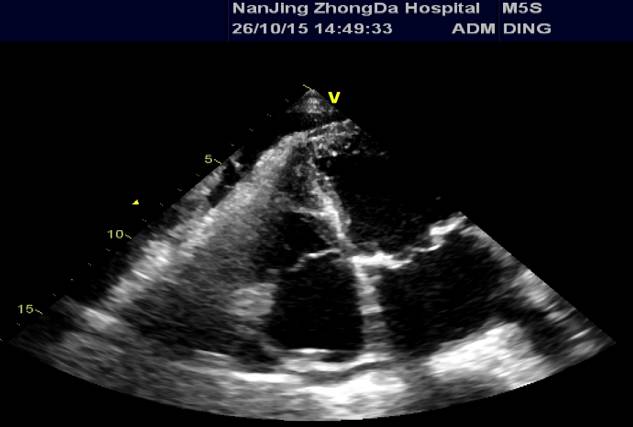

心超(2013-02-01)LA 5.3 RA 4.6 RV 2.7 LV 5.6 LVEF 0.60 TR 3.4(PG=45mmHg)二尖瓣前叶脱垂伴中-重度关闭不全 左心房、右心房、左心室扩大 主动脉瓣钙伴轻中度关闭不全 三尖瓣中度关闭不全 肺动脉高压。

\u000b心超(2015-09-22):二尖瓣前叶脱垂伴中度关闭不全、主动脉瓣钙化,LA(5.4)、RA(4.2)、LV(6.4)、 LVEF 0.40,三尖瓣中度、主动脉瓣中度返流、肺动脉高压(PG=36mmHg)、心功能减低 。